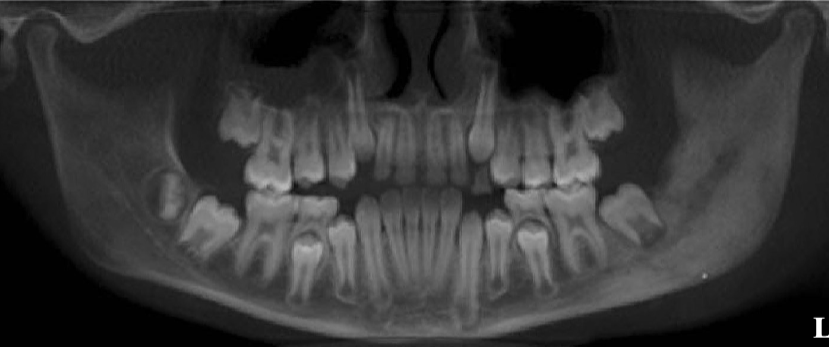

what’s the pathology of the L mandible

diffuse sclerosing osteomyelitis of L angle-ramus of mandible

differentiate between the 2 radiographs

L: osteomyelitis w/ ill-defined, mixed lesion of L body + ramus of mandible, “moth eaten” appearance

R: well-defined radiopaque lesions in max + mand, not osteomyelitis